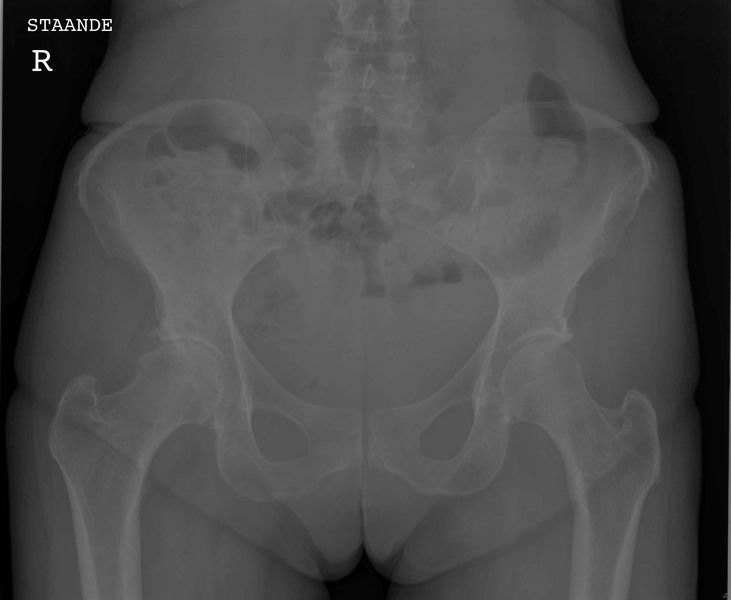

Bekken